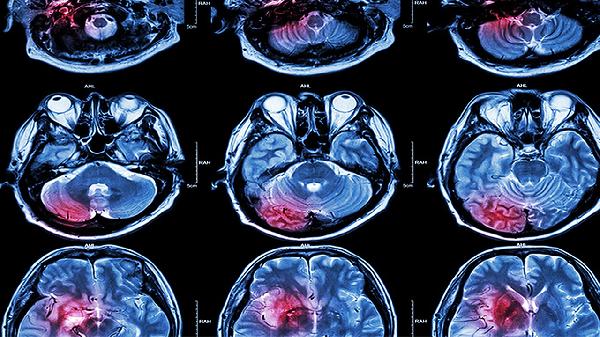

宝宝脑发育不全的症状主要有运动发育迟缓、肌张力异常、语言能力落后、认知功能障碍以及癫痫发作。脑发育不全可能与遗传因素、围产期缺氧、颅内感染、代谢异常或脑外伤等因素有关,通常表现为上述症状中的一种或多种。建议家长及时带宝宝进行专业评估,早期干预有助于改善预后。